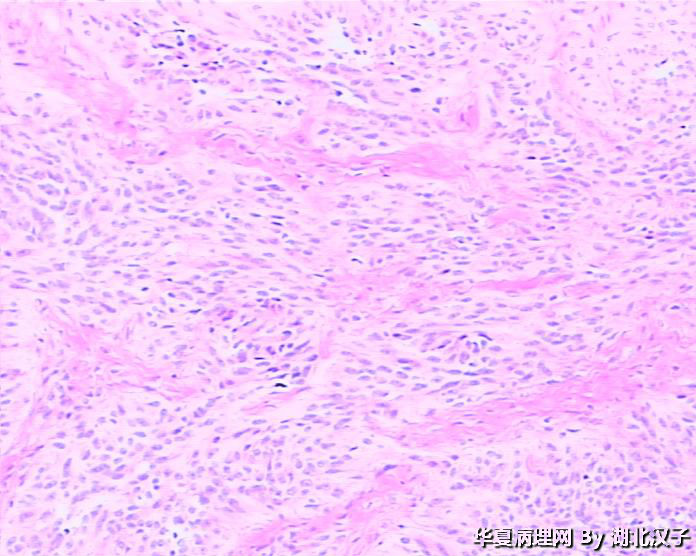

• 宫颈肿物图1

图1

48岁,宫颈肿物

平滑肌瘤,富于细胞?

平滑肌瘤,富于细胞。

平滑肌瘤??

有腺腔样结构,宫颈的上皮状态与图片有相关吗?似巢状浸润。

1、没见到正常宫颈组织;2、没见到肿瘤边缘,如果境界不清则不是平滑肌瘤。